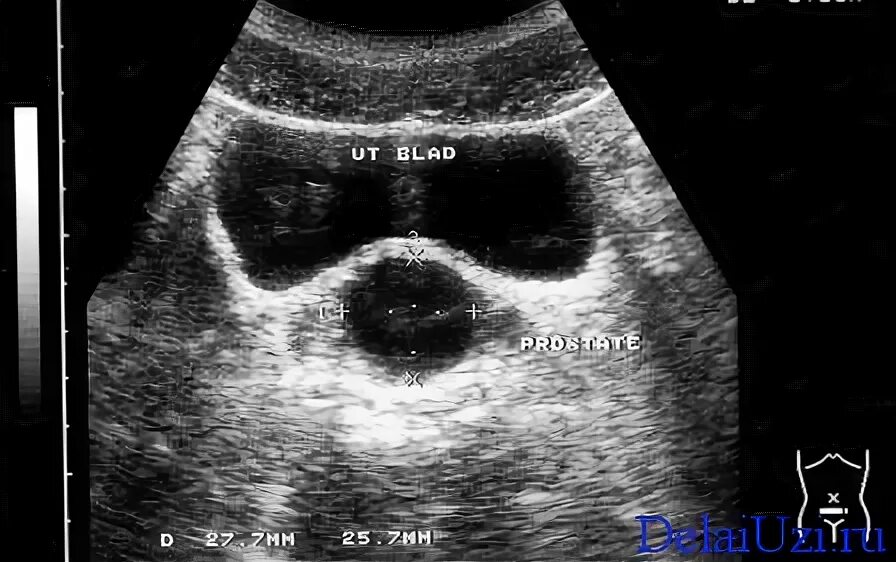

Трансабдоминальное узи